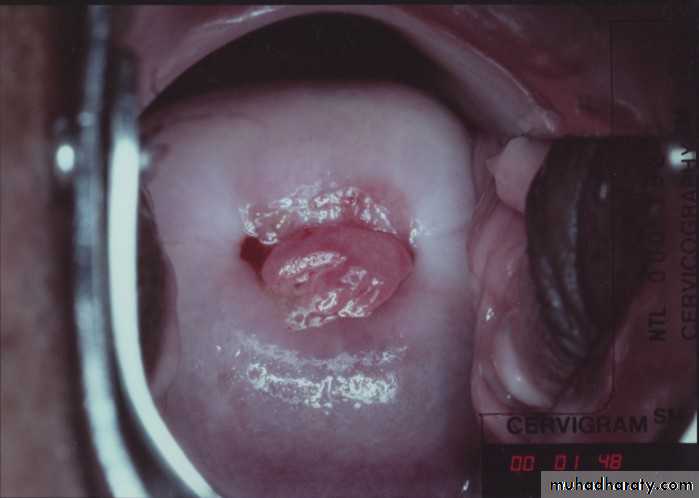

1. Cervical cause

Carcinoma

Polyp

Ectropion